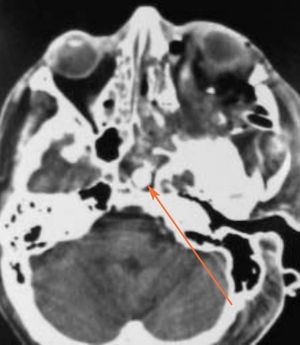

В первой демонстрации на заседании было представлено описание ранения головы Г-ва, 34-х лет, из пистолета «Оса» (ПБ-4-1М) пулей травматического патрона 18х45Т в конфликтной ситуации с расстояния менее 1 м. По данным врачей скорой помощи на месте травмы сознание пострадавшего оценено на уровне глубокой комы.

При осмотре обнаружено входное отверстие раневого канала размером 1,5х2 см округлой формы в правой височной области. Из раны наблюдалось поступление мозгового детрита и умеренное кровотечение.

Ранение представляло собой слепое диаметральное проникающее повреждение правой височно-теменной области головного мозга с дырчатым переломом правой теменной кости (ил. 1). При рентгенологическом обследовании и компьютерной томографии черепа в левой височной доле была обнаружена пуля (ил. 2, 3).

Ил. 3. Схема ранения головного мозга. В области входной раны видны отломки височной кости, в конце раневого канала – пуля патрона 18х45Т

Ил 6. КТ головы пострадавшего М-ва на уровне расположения инородного тела в основной пазухе черепа. Стрелкой указано положение пули патрона 9 Р.А.